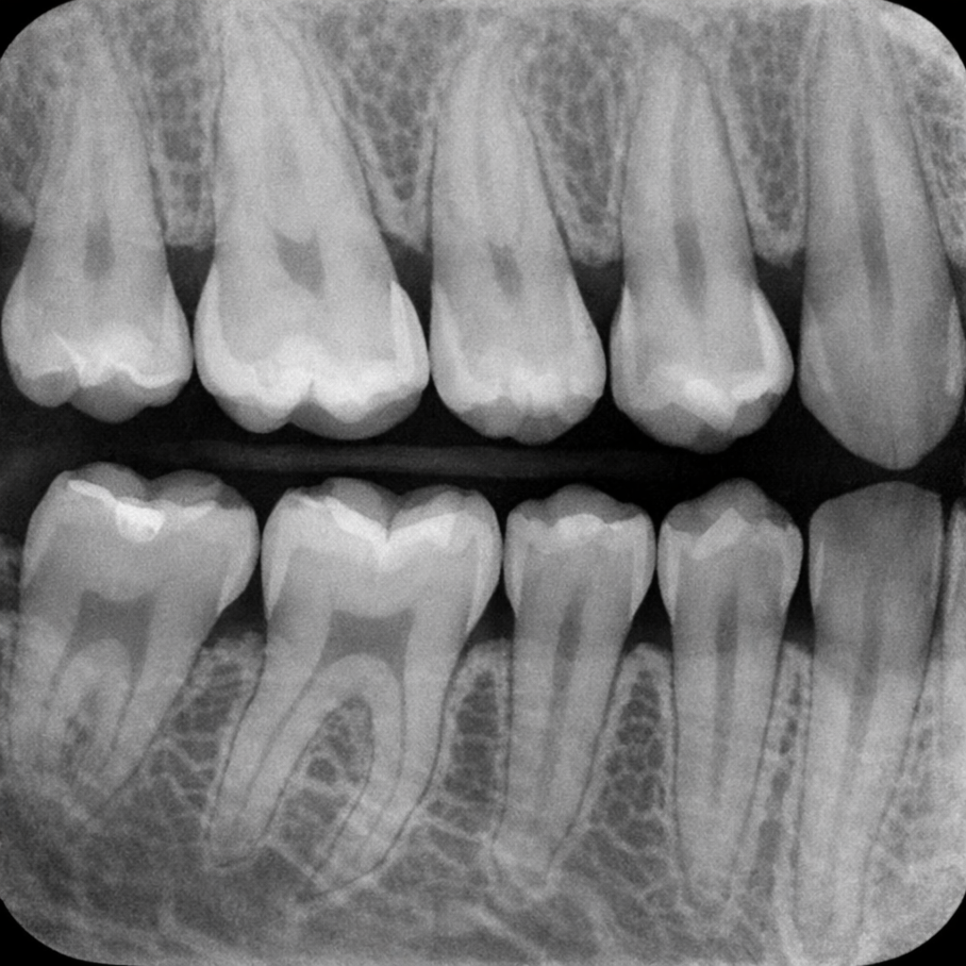

이러한 이유로 인접면 충치는

환자분이 스스로 발견하기보다는

정기검진 과정에서

방사선 촬영(X-ray)을 통해

발견되는 경우가 많습니다.

앞서 말씀드렸듯이

진단하는 가장 확실한 방법은

구내 방사선 사진(X-ray)입니다.

치아 사이를 투과하여 찍는

날개 교합 방사선 사진(bitewing X-ray)은

인접면의 초기 병변까지 비교적

정확하게 확인할 수 있습니다.

육안 검사만으로는

놓치기 쉬운 부위를

영상으로 확인할 수 있어

정기검진 시 X-ray 촬영이

함께 이루어지는 것이

중요한 이유가 여기에 있습니다.

증상이 없다고 해서 인접면 충치가 없다고

단정할 수 없는 것이 바로 이 때문입니다.